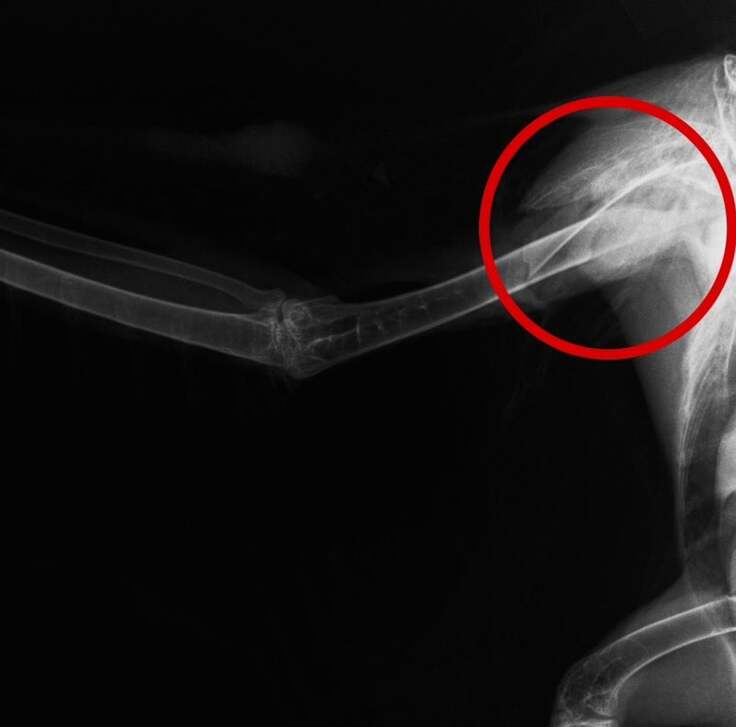

次の日、レントゲンを撮ると、やはり右翼の上腕骨が裂けるような形で折れていました。

骨折をしてしまった時、人間の場合はギプスで骨折箇所を固定し、動かないようにしますが、動物の場合は「安静にしていてください」と伝えても動かないでいてくれるわけではないので難しく、特に鳥の翼の骨折の場合、外から固定しても、動こうとしてギプスがずれてしまったり、取れてしまうこともあります。